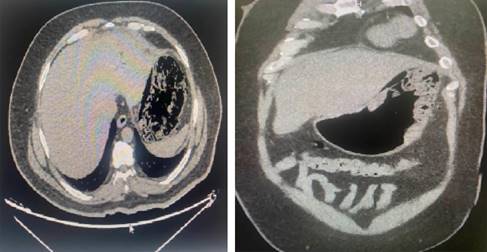

Ante cuadro clínico sugerente de abdomen agudo, se decidió realizar una tomografía computarizada de abdomen urgente, en la cual se describió la presencia de distensión gástrica, asociado a neumatosis difusa (Figura 1).

Figura 1: Se observa el estómago distendido, con mucosa engrosada de manera difusa y paredes con neumatosis extensa.